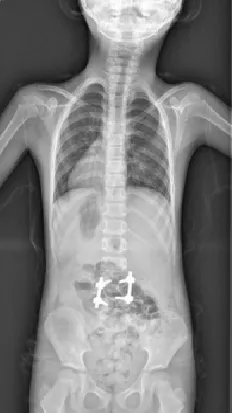

▲ 女,3岁4个月,先天性脊柱侧弯半椎体畸形

▲ 女,7岁,先天性脊柱侧弯半椎体畸形